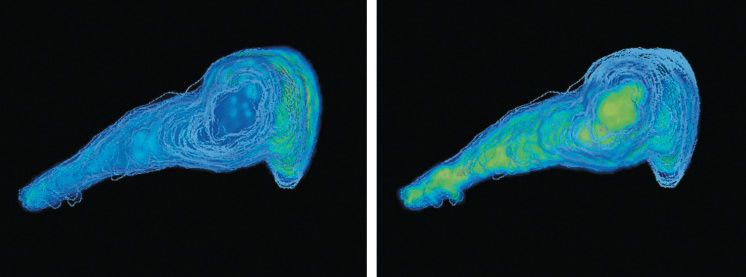

The unique ability of MALDI imaging to visualize molecules in situ has significantly advanced the study of this complex biology. Figure 4 shows a two-dimensional (2D) image of a rat epididymis head with highlighted peptides possibly involved in the maturation of sperm during its transit through the organ (14). Figure 5 illustrates the latest work in Pineau's lab: the creation of 3D images (15). The process of capturing a 3D MALDI imaging model of an organ begins with making many hundreds (or thousands) of sections through the organ. Each section is measured and the data are combined in software to create the final picture. The resulting data sets are huge-in the terabyte range-but once completed, a dataset can be mined for information for many years.

Figure 4: Molecular image of sperm transit in the rat epididymis by MALDI imaging MS. Peptides specific to maturing spermatozoa during epididymal transit can be visualized simultaneously. Signal overlay of three specific peptides corresponding to m/z 5470, 6177, and 18,746 is visualized in different colors. An 80-µm lateral image resolution is mandatory to resolve the organ structures.

Figure 5: Three-dimensional mass spectrometry imaging view of a rat epididymis head. PLSA computation in SCiLS software with restricted mass range (m/z 250-1650). Left: m/z corresponding to a metabolite localized in the vas efferens area. Right: m/z corresponding to a metabolite expressed along the tubule.